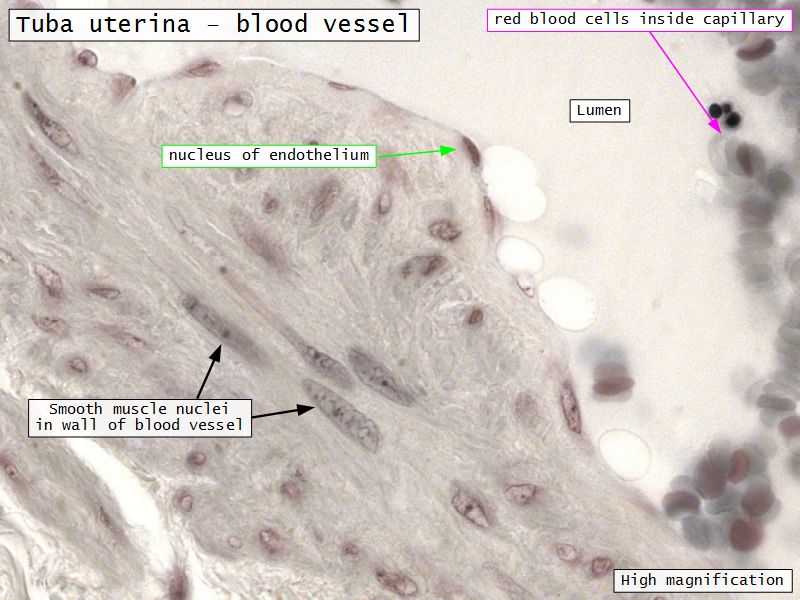

Tuba uterina

Tuba uterina

- Muscular tube

- Most frequent site of fertilization

- Conveys zygote to uterus

- Four regions

- Three layers

Three layers

- Mucosa

- Muscular layer

- Serosa

Muscular layer

- Ill-defined

- Inner circular

- Outer longitudinal

- Play role in moving zygote towards uterus

Serosa

- Simple squamous epithelium

- Contains

- Blood vessels

- Lymphatics

- Nerves